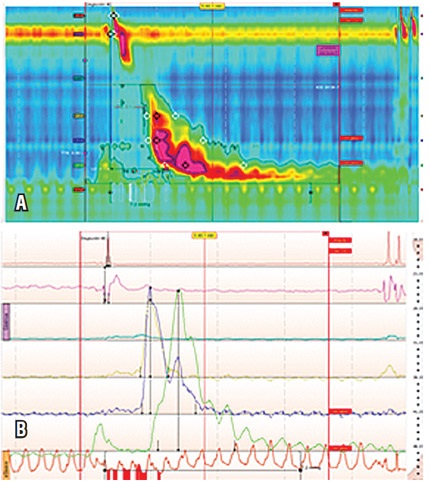

Paciente femenina de 45 años con síntomas típicos de enfermedad por reflujo gastroesofágico (ERGE), ocasionados por pirosis y regurgitación, sin disfagia ni dolor torácico, con síntomas refractarios al manejo con inhibidores de bomba de protones (IBP) y con EVDA que demostró hernia hiatal y esofagitis. Dada la refractariedad al manejo se indicó estudio con MAR que evidenció 3 de 11 ondas con ICD por encima de 5000 mm Hg/cm/s, y una de ellas con un valor superior a 8000 mm Hg/cm/s (12562). La presión intrabolo durante el trazado fue normal (tablas 1 y 2; figura 2).